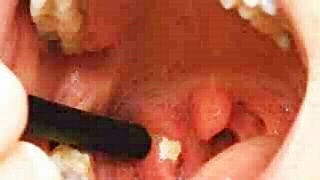

오늘은 편도결석 제거법과 그 원인에 대해 포스팅하도록 하겠습니다. 편도결석은 음식 잔여물과 세균이 편도의 작은 홈에 결합하여 형성되는 쌀알만 한 노란색의 입자입니다. 입에서 나는 냄새와 불편한 느낌이 주요한 증상이지만, 이는 심각한 건강 이슈를 야기하지는 않습니다. 그러나 입 냄새로 인해 주변 사람들이 불편해하고, 이로 인해 인간관계에 어려움을 겪을 수 있으므로, 적절한 해결책을 찾는 것이 중요합니다.

2. 직접 제거: 편도는 매우 민감한 부위이므로, 칫솔 등 딱딱한 도구로 제거하려 하면 오히려 손상을 입힐 수 있습니다. 따라서 면봉을 이용해 부드럽게 결석을 제거하는 것이 좋습니다. 그러나 잘못 제거하면 출혈이나 감염 등의 부작용이 있을 수 있으므로 주의가 필요합니다.